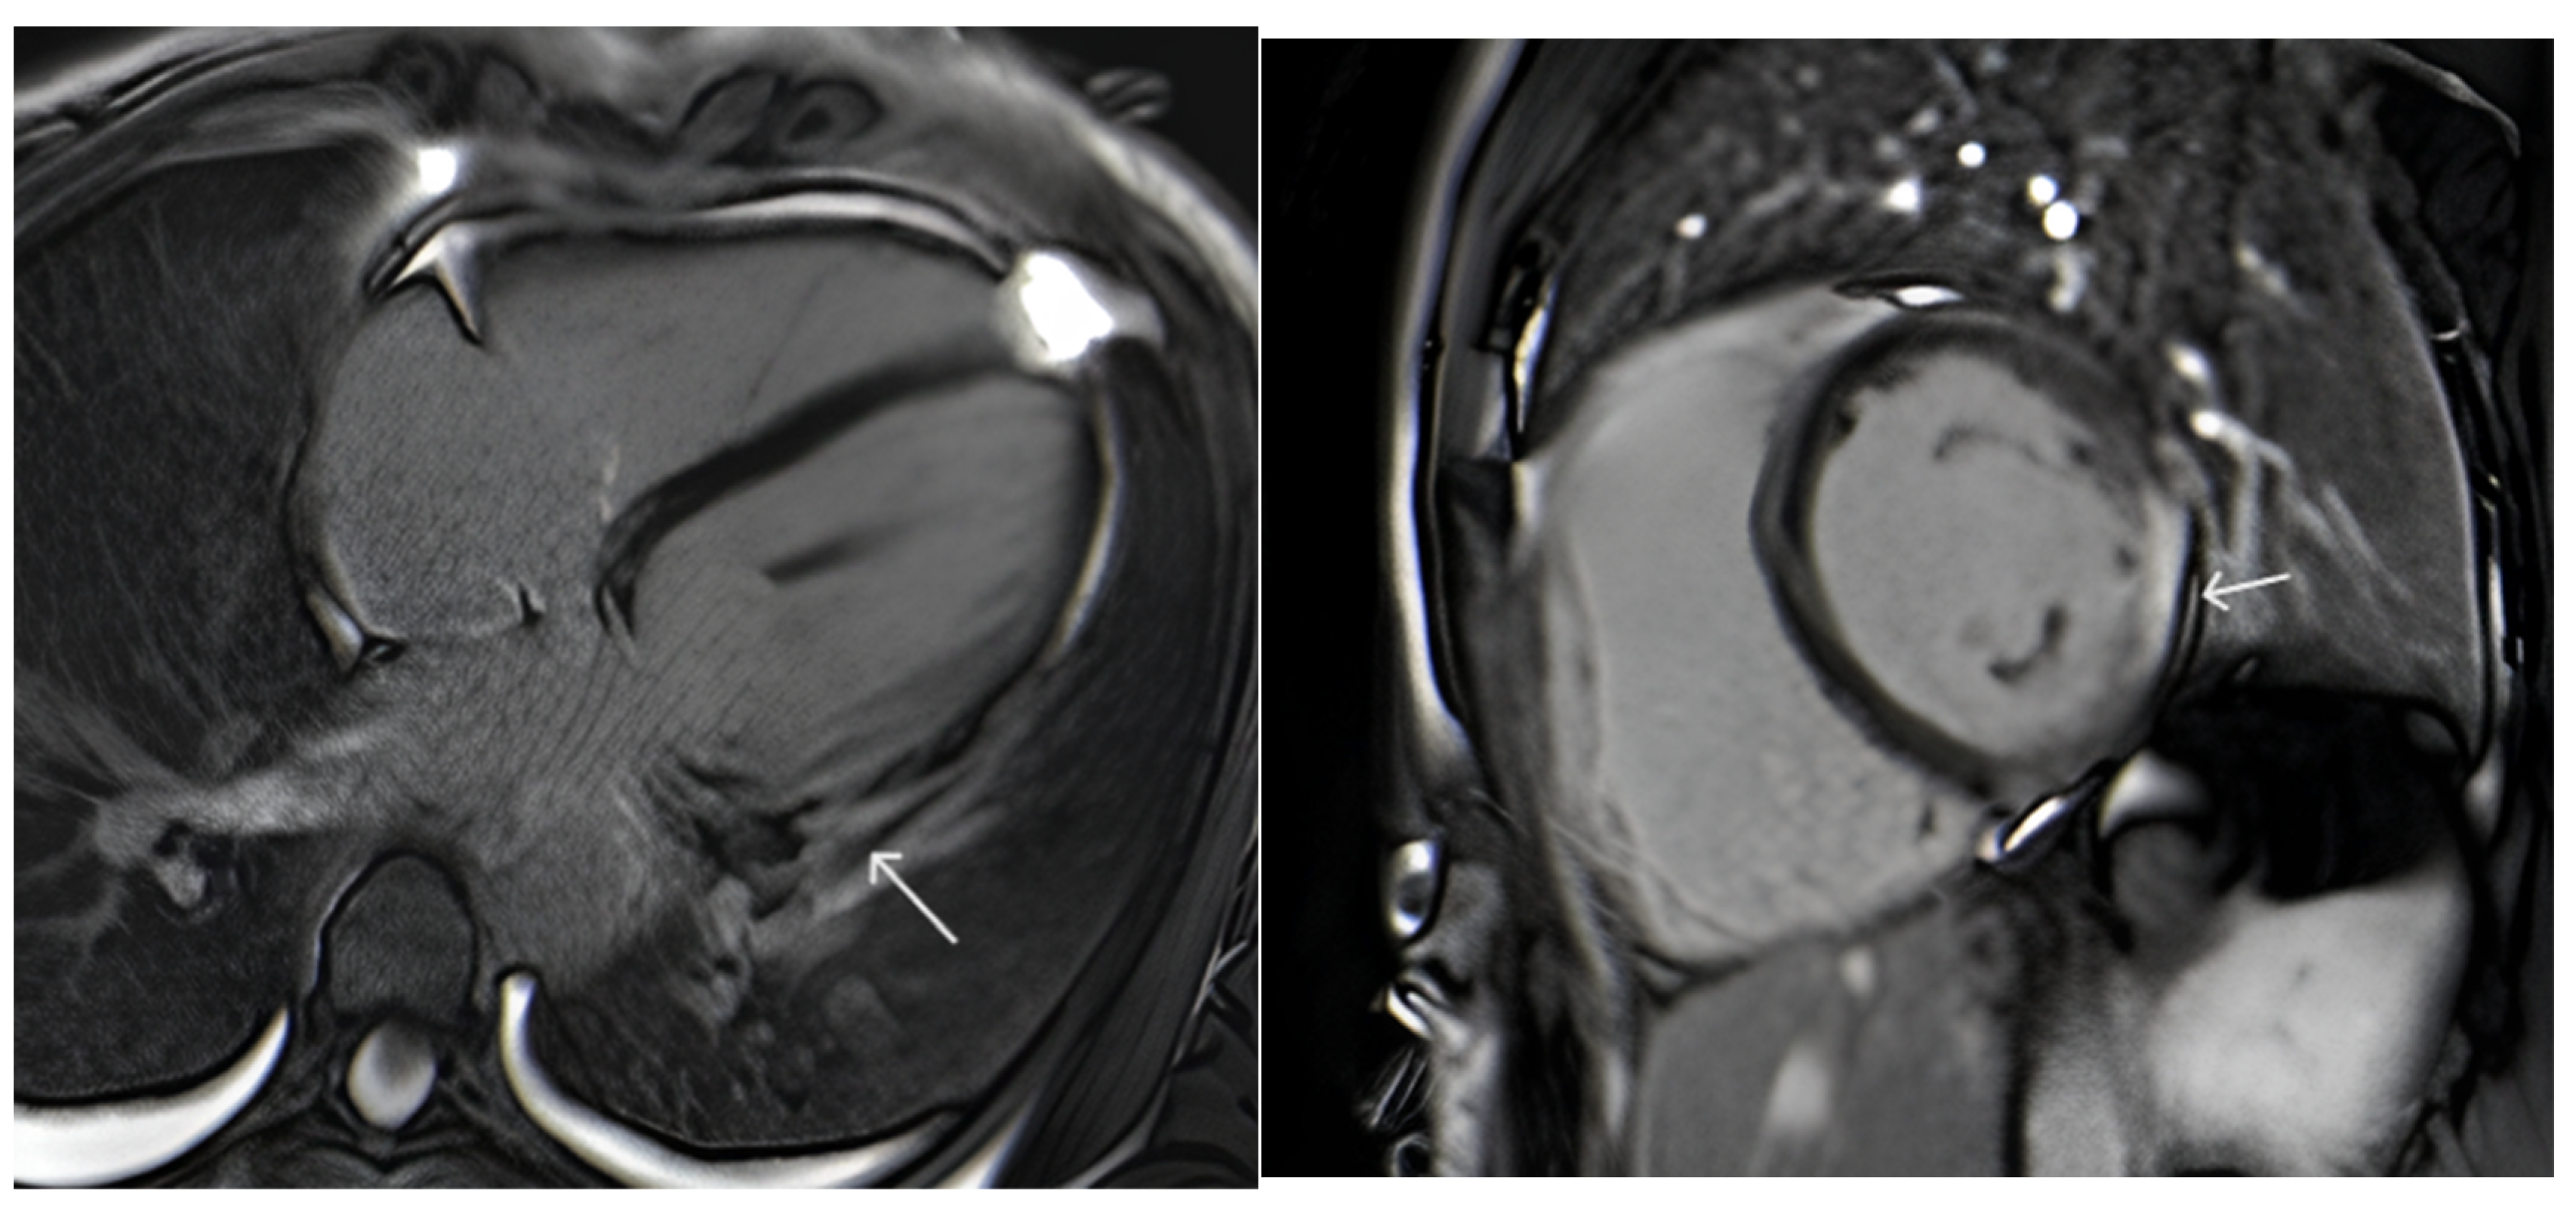

Due to the undetermined cause of the VT, the patient underwent thorough cardiac assessment. A computed tomography (CT) angiogram was performed to exclude significant coronary artery disease, and the coronaries showed neither atherosclerotic plaques nor narrowing. Cardiac magnetic resonance (CMR) showed a slightly enlarged left ventricle with mildly reduced ejection fraction (Figure 1). The LV wall thickness was normal. In cine images, there was hypokinesia of the basal lateral wall. Intensive transmural late gadolinium enhancement (LGE) was present in the lateral wall (Figure 2). T2 mapping showed myocardial edema predominantly in the lateral wall (Figure 3). T1 mapping revealed diffuse myocardial fibrosis in the LV myocardium (Figure 4). In addition, 18F-fluorodeoxyglucose-positron emission tomography (FDG-PET) scan excluded inflammatory myocardial diseases such as sarcoidosis.

Figure 2.

Short axis and four chamber LGE images show transmural enhancement in the lateral wall (arrows).